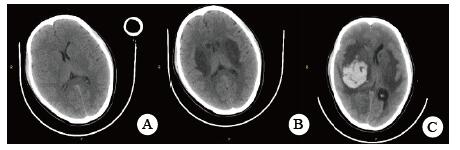

当晚20时到达本院,入院时患者昏迷,血压低、心肌损伤、轻度心衰, 低氧血症, 肝损伤。相关实验室检查:血气PaO2 44 mmHg,生化指标谷丙转氨酶(ALT)528.8 U/L,谷草转氨酶(AST)780.9 U/L,胆红素正常,尿素氮(BUN)3.6 mmol/L,肌酐(Cr)125.7 μmol/L,血糖7.88 mmol/L,心肌肌酐蛋白(cTnT)55.94 ng/mL,N末端B型利钠肽原(NT-pro BNP)495.7 pg/mL,神经元特异性烯醇化酶(NSE)47.46 ng/mL。胸部CT未见明显异常(图 1),头颅CT未见明显异常(图 2A)。给予异甘草酸镁保肝,乙酰半胱氨酸抗氧化,兰索拉唑保护胃黏膜,并予血液灌流治疗一次。

| 图 1 患者入抢救室时肺部CT影像 |

次日晚间收住入院。住院第2天监测血压99/72 mmHg。实验室检查:cTnT 245.4 ng/L,NT-pro BNP 18.57 pg/mL,BUN 2.68 mmol/L,Cr 40.5 μmol/L,血钾3.82 mmol/L。血气:PO2 116 mmHg,pH 7.498, Lac 1.58 mmol/L。并CRRT治疗:治疗前APTT为32.2 s,阿加曲班抗凝,治疗剂量40 mL/(kg·h)。第3天继续CRRT治疗,阿加曲班抗凝,监测APTT为62.9 s(为正常值2倍)。第4天停CRRT, 记录自发尿量1 920 mL /24 h。第5天神志逐步转清,有指令动作,自主呼吸良好,停机械通气。脱机拔管后查颅脑CT双侧基底节区及脑干低密度影, 考虑中毒性脑病改变(图 2B),胸部CT未见明显异常。监测APTT为26.7 s。第7天患者再次昏迷,并有呼吸急促,脉氧下降。再次行气管插管呼吸机支持。监测肝功能进一步好转(ALT 187.7 U/L,AST 92.2 U/L)。第8天17时发现患者瞳孔不等大,左侧3.5 mm,右侧4.5 mm, 对光反射消失,即查颅脑CT示右侧基底节区出血(图 2C)。家属要求保守治疗。第9天患者处于深昏迷状态,家属放弃继续治疗出院。出院一周后随访患者死亡。

哒螨灵口服中毒后机体细胞内呼吸功能抑制,导致细胞缺氧,无糖酵解,乳酸快速堆积,机体迅速出现代谢性酸中毒,重要脏器灌注不足,早期即可表现肝功能异常甚至肝衰竭;心肌酶谱增高,心肌收缩力减低,胰腺功能受损,血淀粉酶增高,血糖应激性增高[3]。由于人体脑组织供应的血流非常丰富,因此对缺氧表现也非常敏感。但哒螨灵中毒并发脑病报道较少,并发脑出血者罕见。该例患者中毒后出现恶心呕吐,提示该药对胃肠道有刺激性;后出现多系统损伤。早期即出现意识障碍,并渐加重至昏迷,有脑神经元损伤,但早期头颅CT未见明显异常;患者有严重低血压,需要大剂量血管活性药物维持血压;患者严重低氧血症,需要呼吸机支持,但肺部影像学未见明显异常;患者有乳酸酸中毒、肝肾功能损伤和心肌受损,但上述损伤大多在支持治疗2~4 d后完全正常或出现明显好转。但第5天头颅CT提示患者出现中毒性脑病表现,患者神志在短暂好转后又再次恶化,第8天原右侧基底节区水肿部位出现脑出血。